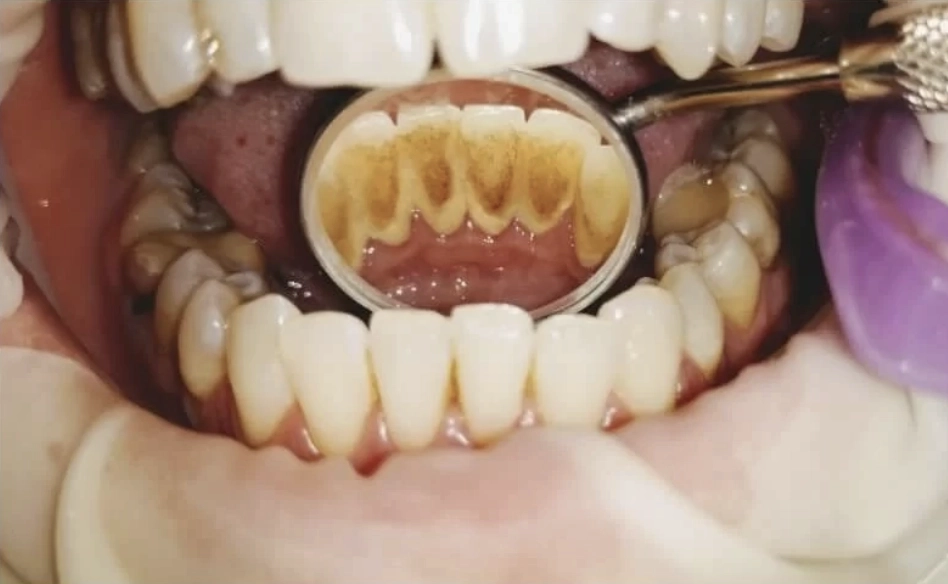

Dantų akmenų šalinimas (profesionali burnos higiena su air flow) – tai svarbiausia profilaktinė procedūra, leidžianti išvengti karieso, dantenų uždegimo ir periodonto ligų. Mūsų klinikoje naudojama moderni įranga užtikrina maksimalų komfortą ir nepriekaištingą švarą net sunkiai pasiekiamose vietose.